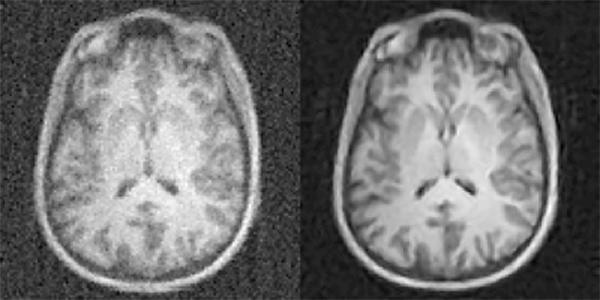

A radiologist's ability to make accurate diagnoses from high-quality diagnostic imaging studies directly impacts patient outcome. However, acquiring sufficient data to generate the best quality imaging comes at a cost - increased radiation dose for computed tomography (CT) and positron emission tomography (PET) or uncomfortably long scan times for magnetic resonance imaging (MRI). Now researchers with the Athinoula A. Martinos Center for Biomedical Imaging at Massachusetts General Hospital (MGH) have addressed this challenge with a new technique based on artificial intelligence and machine learning, enabling clinicians to acquire higher quality images without having to collect additional data. They describe the technique - dubbed AUTOMAP (automated transform by manifold approximation) - in a paper published today in the journal Nature .

"An essential part of the clinical imaging pipeline is image reconstruction, which transforms the raw data coming off the scanner into images for radiologists to evaluate," says Bo Zhu, PhD, a research fellow in the MGH Martinos Center and first author of the Nature paper. "The conventional approach to image reconstruction uses a chain of handcrafted signal processing modules that require expert manual parameter tuning and often are unable to handle imperfections of the raw data, such as noise. We introduce a new paradigm in which the correct image reconstruction algorithm is automatically determined by deep learning artificial intelligence.

"With AUTOMAP, we've taught imaging systems to 'see' the way humans learn to see after birth, not through directly programming the brain but by promoting neural connections to adapt organically through repeated training on real-world examples," Zhu explains. "This approach allows our imaging systems to automatically find the best computational strategies to produce clear, accurate images in a wide variety of imaging scenarios."

AUTOMAP offers a number of potential benefits for clinical care, even beyond producing high-quality images in less time with MRI or with lower doses with X-ray, CT and PET. Because of its processing speed, the technique could help in making real-time decisions about imaging protocols while the patient is in the scanner.

"Our AI approach is showing remarkable improvements in accuracy and noise reduction and thus can advance a wide range of applications," Rosen says. "We're incredibly excited to have the opportunity to roll this out into the clinical space where AUTOMAP can work together with inexpensive GPU-accelerated computers to improve clinical imaging and outcomes."